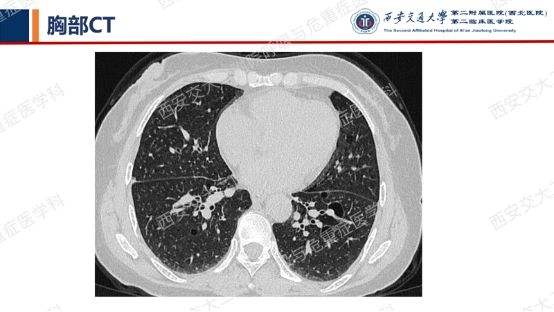

结合以上病史及胸部CT,您的初步考虑?还需要哪些检查?